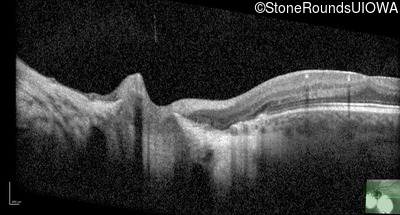

Age at visit: 2 months (Visit 4)